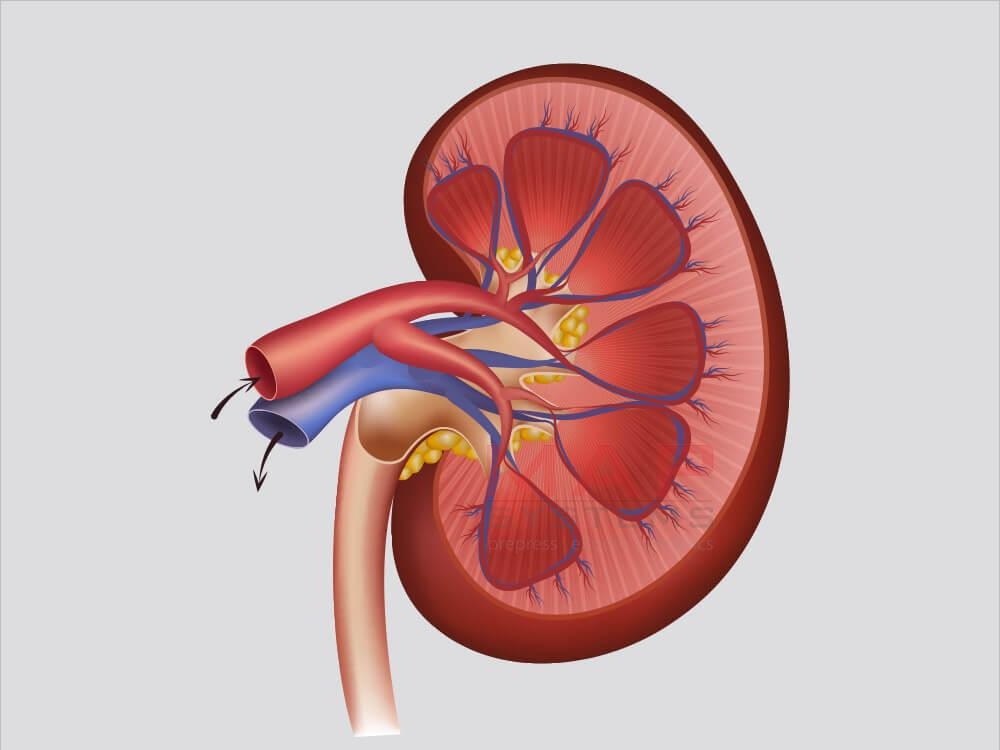

Интраренальная лоханка: рентгеновские снимки и примеры